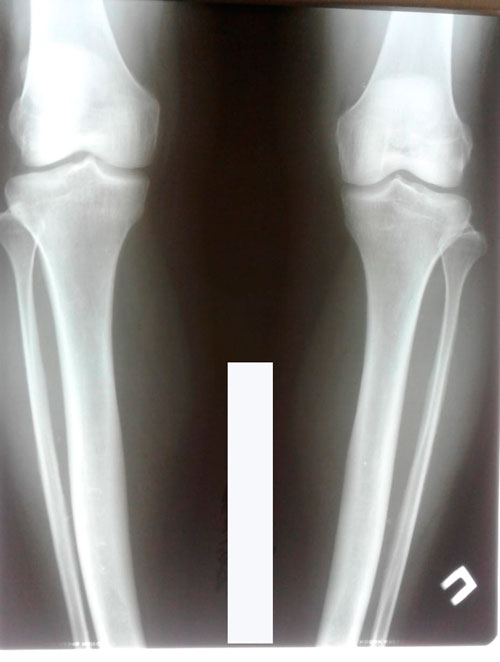

Дата операции 22.06.2018г.

Дата снятия - 02.11.2018г.

Срок сращения - 98 дней.